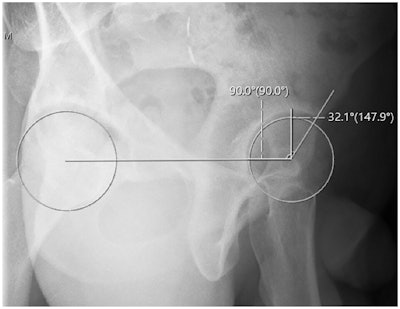

In this study, the team investigated whether their novel method, which uses standard x-ray viewing tools to generate a true horizontal reference line and best-fit circles on each femoral head, may allow for more precise assessments.

Anterior center edge angle measurement utilizing a horizontal reference line. Orthopedic Journal of Sports Medicine

According to the results, the mean ACEA value obtained using the traditional method was 39.72°, and the mean ACEA value obtained using the novel method was 37.68° (p = 0.36). Intrarater reliability for the novel method was found to be strong (ICC = 0.805-0.966) in all instances.

Meanwhile, interrater reliability was also found to be strong in all instances using the horizontal reference line (ICC = 0.831-0.902), but was weak for two of three reviewers using the traditional method (ICC = 0.42, 0.585, and 0.769), the researchers reported.